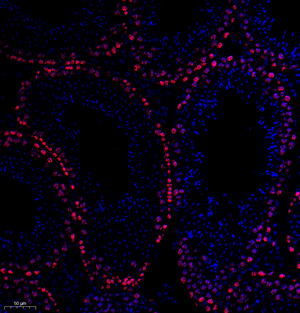

| IF analysis of ki67 (GB111141). Sample: Mouse testis (Paraffin), 4% PFA (G1101) 12-24h. Antigen retrieval: TE buffer (pH 9.0) (G1203),98°C,20min. Blocking buffer: 3% BSA in PBS (GC305010), RT, 30min. Primary antibody: 1: 600, 4°C overnight. Secondary antibody: Cy3 conjugated Goat Anti-Rabbit IgG (H+L) (GB21303), 1: 300 RT, 1h. |